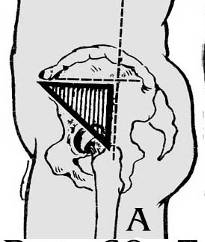

Рисунок 1. Иммобилизационная шина Дитерихса

1. Шину накладывают непосредственно на одежду, если же ее приходится накладывать на голое тело, то под нее подкладывают вату, полотенце, одежду пострадавшего; на конечностях необходимо иммобилизовать при травме бедра – все 3 сустава конечности;

2. Накладывание шины: подошвенную часть шины фиксируют бинтом к подошвенной поверхности стопы; наружную (наружный костыль) более длинную часть раздвигают и закрепляют с таким расчетом, чтобы она начиналась от подмышечной впадины и, вставленная в металлическую пружину в подошвенной части, выступала за нее на 8—10 см; внутреннюю часть шины (внутренний костыль) подготавливают таким образом, чтобы она упиралась в пах и проходила через металлическую проушину подошвенной части, выступая за нее на 8—10 см; конечную (шарнирную) часть сгибают под углом 90° и вставляют в особый паз конца наружной части шин; на конечности шину фиксируют циркулярными ходами бинта; вверху наружную часть шины фиксируют двумя ремнями. При помощи палочки-закрутки осуществляют вытяжение за подошвенную часть шины

3. При закрытых переломах во время наложения шины необходимо произвести легкое вытяжение по оси конечности за дистальную часть ноги и в таком положении зафиксировать конечность;

4. Необходимость защиты от переохлаждения.

При неправильной иммобилизации смещение отломков во время перекладывания и транспортировки может превратить закрытый перелом в открытый, подвижными отломками могут быть повреждены крупные сосуды, нервы. Дополнительная травма окружающих тканей может привести к развитию шока.